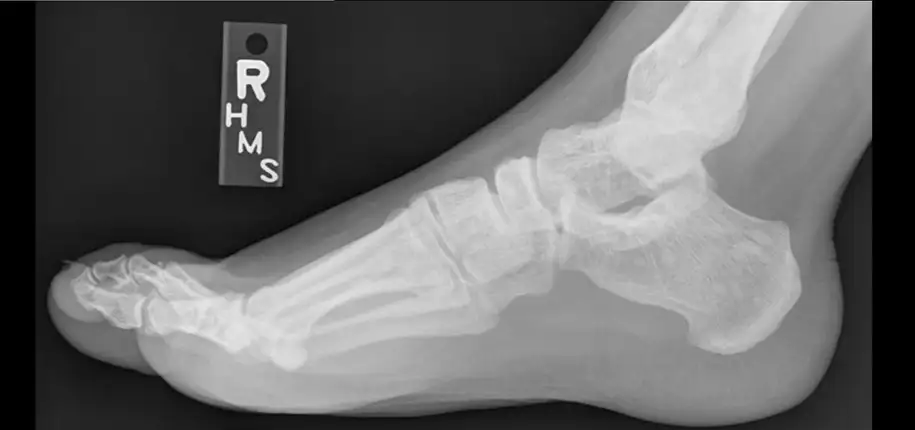

We’re used to the ways visible light interacts with the world around us. Some things are transparent, or see-through, like a window. Other things are translucent, where some of the light passes through and some is blocked, like a lampshade. Other things are opaque and block light, like metal, wood, or a person. Just like visible light, x-rays are blocked more by some materials than by others. In the human body, bones block x-rays very well, while skin and muscle block them less. Parts of the body that contain air, like lungs, block x-rays even less. The amount of blocking, or attenuation, of the x-ray beam is related to density. Generally, the more dense an object, the better it blocks the x-ray beam.

When an x-ray beam passes through a person, we can collect the energy on the other side to see what body parts blocked the beam. Just like the first visible light cameras used film to capture an image, the first x-ray cameras did, too. When the x-ray beam hit the film, it changed the color of the film, and that allowed the x-ray to be turned into a picture that could be seen with the eye. Just like most cameras we use these days are digital, though, so are many modern x-ray systems.

Pictures made using x-rays help doctors make many important diagnoses. They can help us see pneumonia in the lungs or a broken bone, just to name two examples.